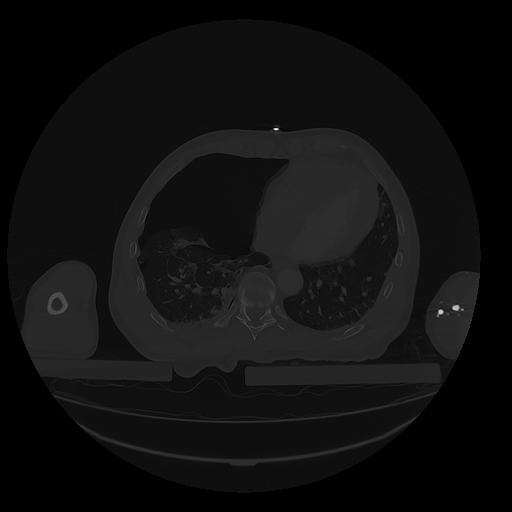

31 PULMON,CE,Vol,1.0,PULMON,,